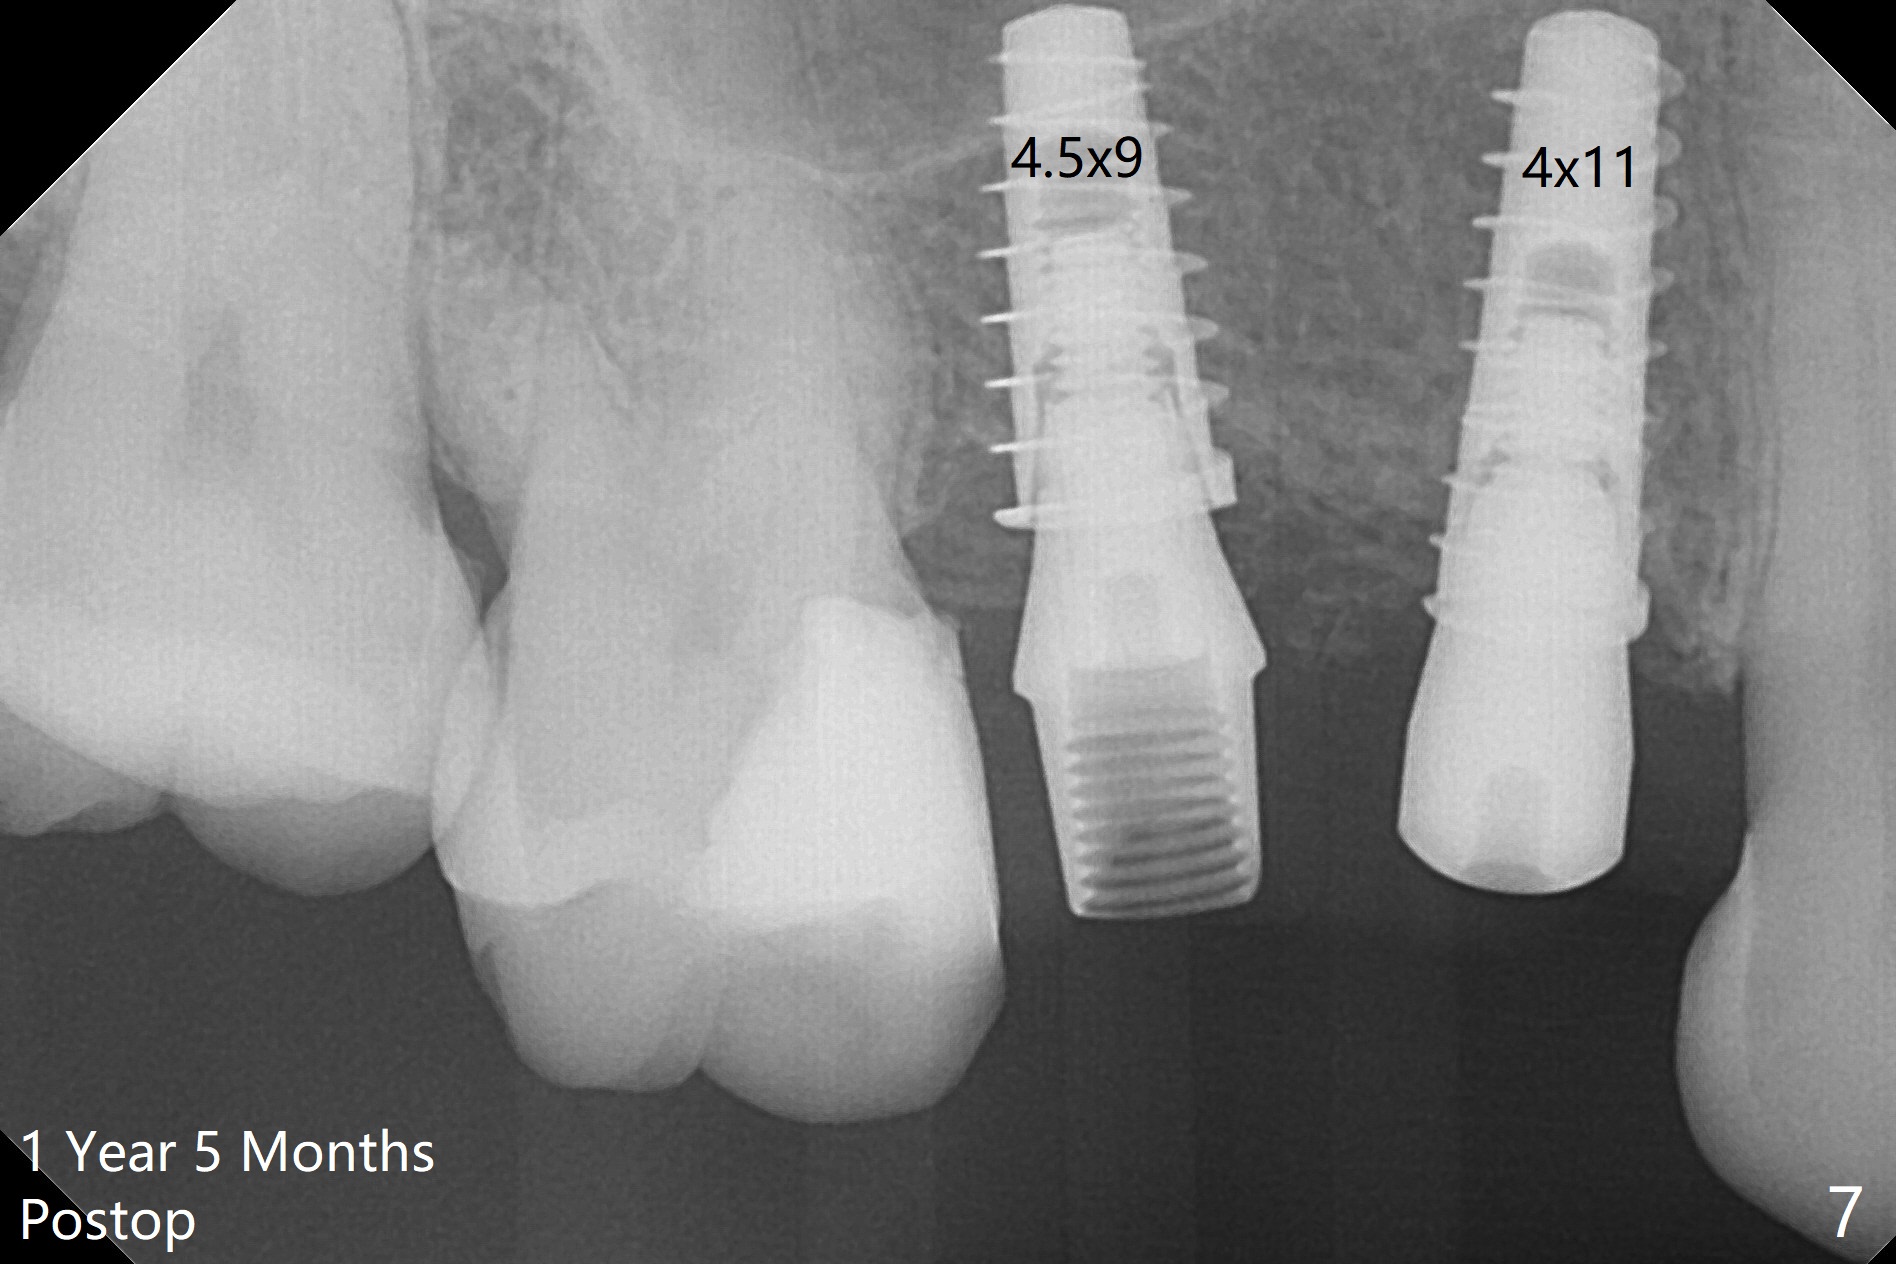

At the healed site (#5), insertion torque of a 4x11 mm implant is >50 Ncm (Fig.4). Because of supraeruption of the tooth #28 (Fig.6 arrow), a healing abutment (4x2 mm) is placed at #5 (data not shown), while a pair abutment (4.5x4(2) mm) is placed at #4 (Fig.4,6). In fact a splinted provisional is placed at #4 and 5 with a low occlusal table. There is no apparent bone loss 1 years 5 months postop (Fig.7). In fact the implants either perforate the palaatal or buccal (B) plate, as revealed by CBCT (1 year 6 months postop, immediately post cementation, Fig.8,9). It appears necessary to have guided surgery and smaller implant in the narrow ridge.